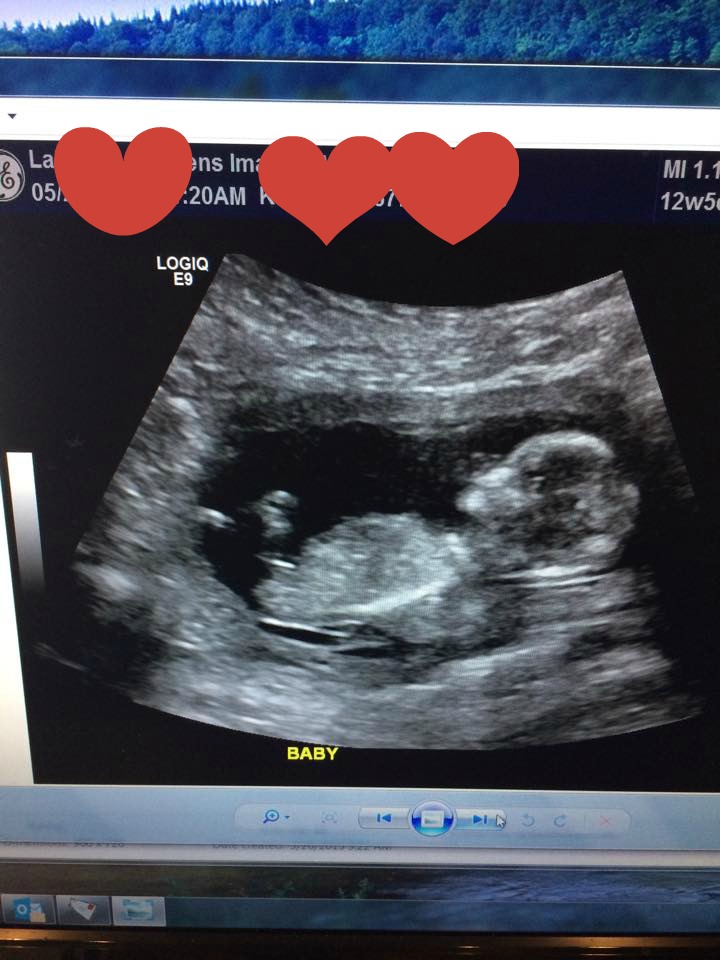

Hi ladies. We did IUI to conceive this baby. We had our NT scan on Tuesday and while I wanted to be team green to potentially avoid GD, the tech gave us a peek without asking if we wanted to. There didn't seem to be anything between the legs. My son's ultrasound was a well defined boy part at 15 weeks. I know this is earlier, but I don't want to get my hopes up. Or maybe baby had it tucked, or something. I was going through the pics they gave us and I'm confused by the nub. Can you help me? Thanks!

Attachment 25501

Exactly which gestation is this? I'm on the fence on this one.

Baby measuring 13+6 by CRL, by LMP 13+2.

I think I'm going for a slight boy lean on this one, my little boys nub shot was very similar to this.

I'm thinking since this is in week 13, I'll lean girl, even though I would lean more boy if it were around 12+0 weeks. GL!